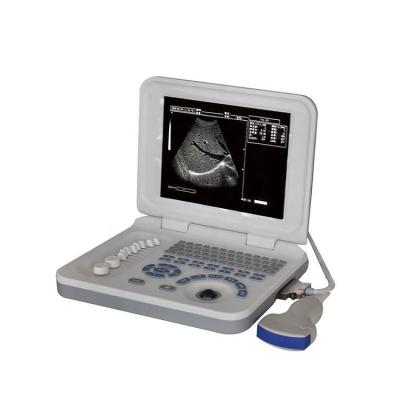

Portable Abdomen CE ISO Certificate Ultrasound Scanner Machine

Price: Negotiable

MOQ: 1.0 Pieces

Delivery Time: Negotiable

Brand: Medco

Contact Now

Gynecological Examination Device Portable Abdomen Pregnancy Ultrasound Scanner

Price: Negotiable

MOQ: 1 Piece

Delivery Time: Negotiable

Brand: Medco

Contact Now